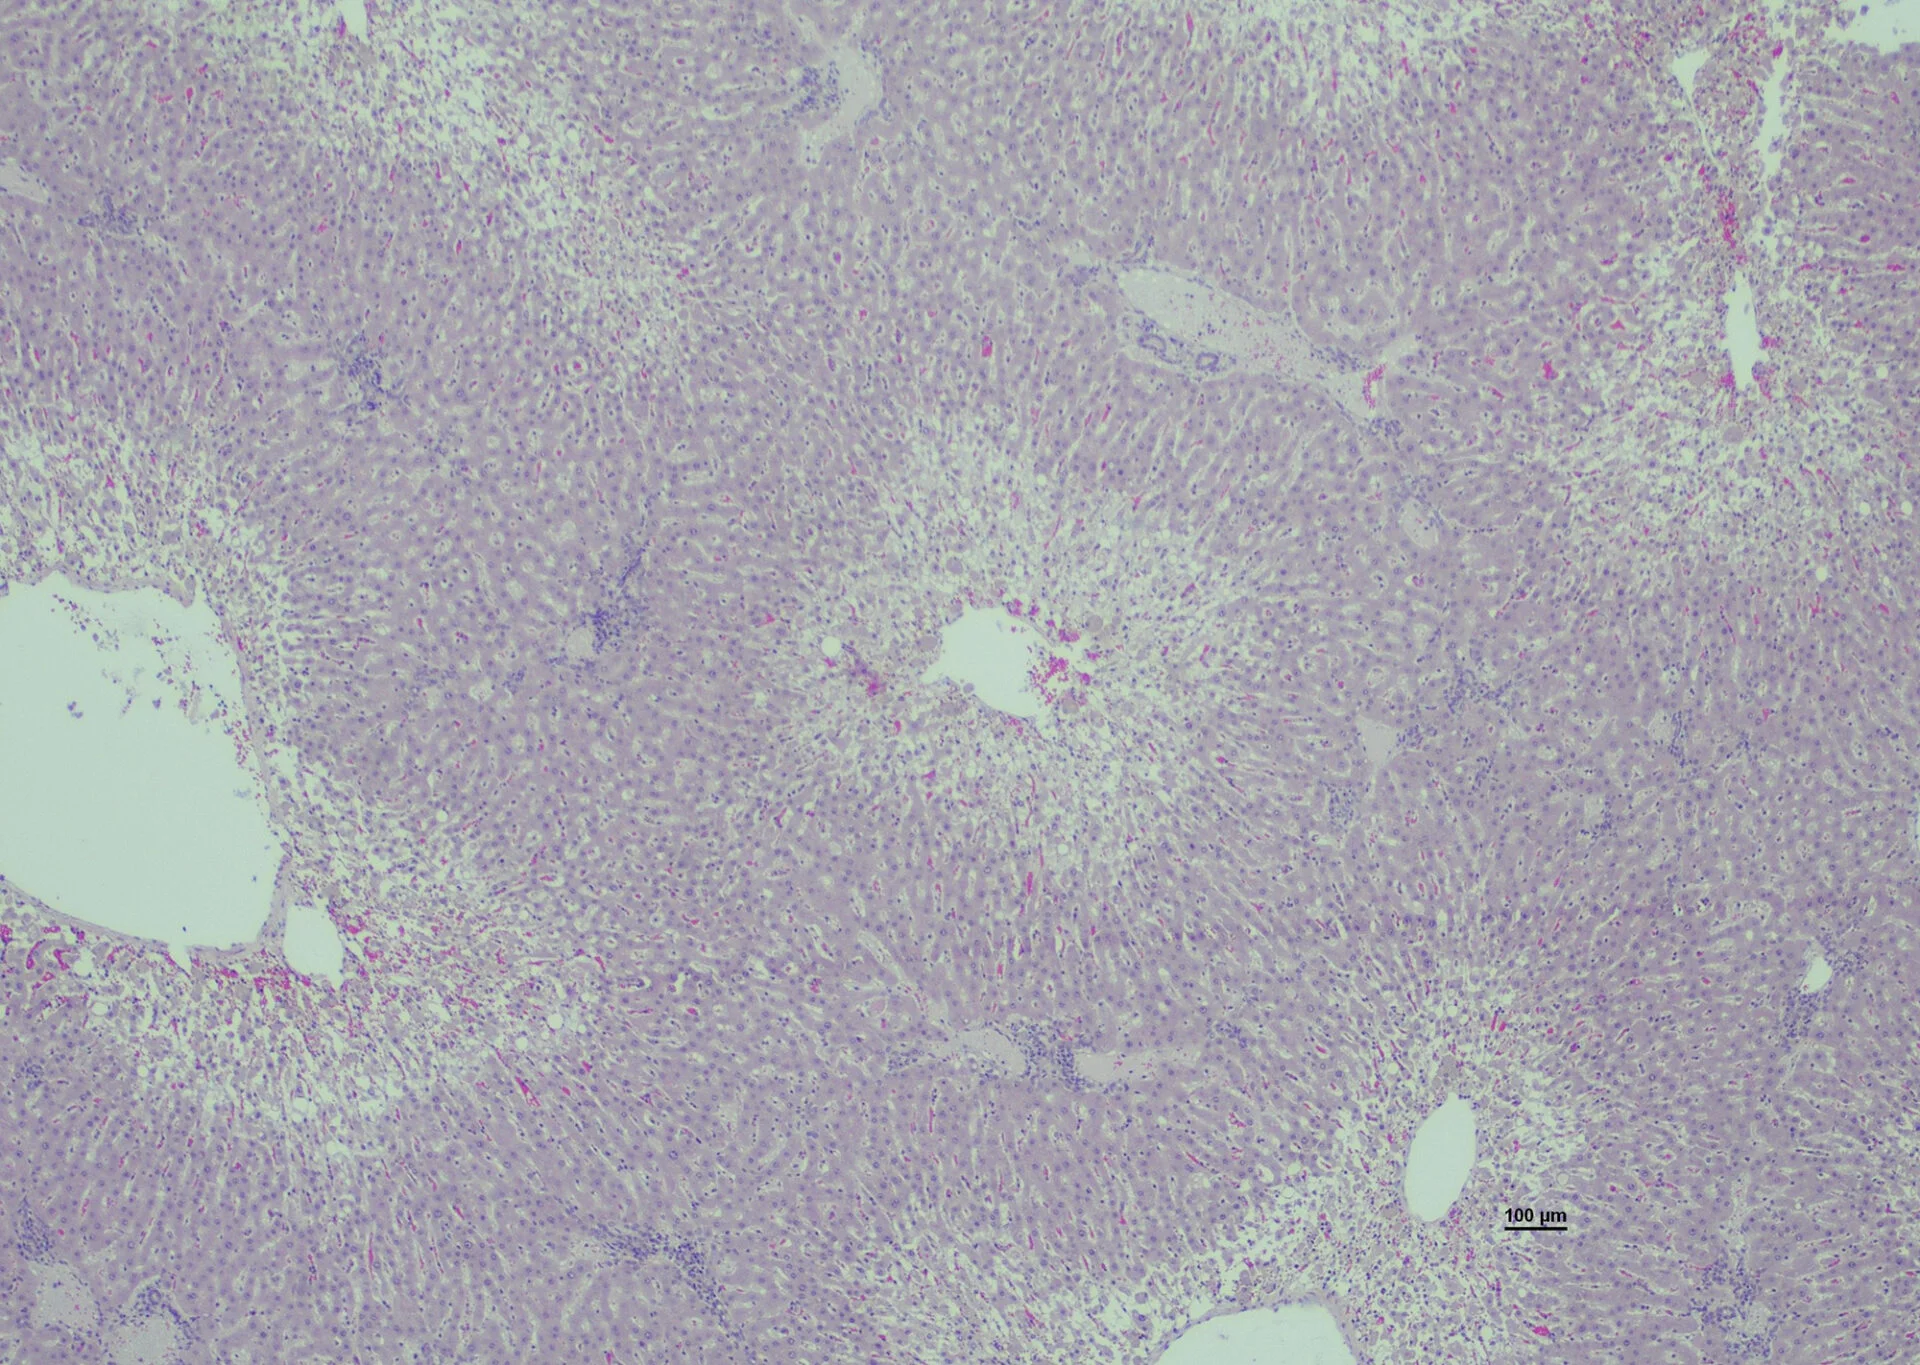

Lisäksi pernan viillospinta oli vetisen valuvaa. Toisella oli voimakas askites ja vatsaontelossa oli noin viisi litraa kirkasta nestettä. Histologisesti kummankin maksa oli hyvin voimakkaasti rappeutunut ja rasvoittunut.

Kuvassa on lopetetun uuhen maksa, jossa on voimakas sentrolobulaaristen maksasolujen rappeuma ja rasvoittuminen. Kuva: Ruokavirasto